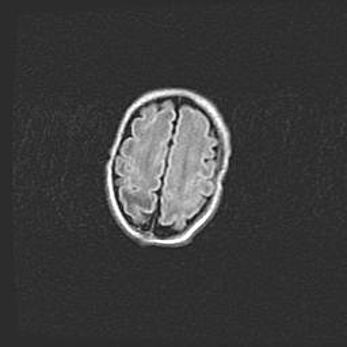

Церебральная ишемия II.

Возраст: 5 дней

Вес: 3400 г

Пол: женский

Окружность головы: 35 см

Срок гестации: 39 недель

Церебральная ишемия – это заболевание, характеризующееся недостаточностью (гипоксией) либо полным прекращением (аноксией) снабжения мозга кислородом по причине закупорки одного или нескольких сосудов. Это приводит к  что метаболическим расстройствам различной степени тяжести в тканях головного мозга, развитию коагуляционных некрозов и гибели нейронов.